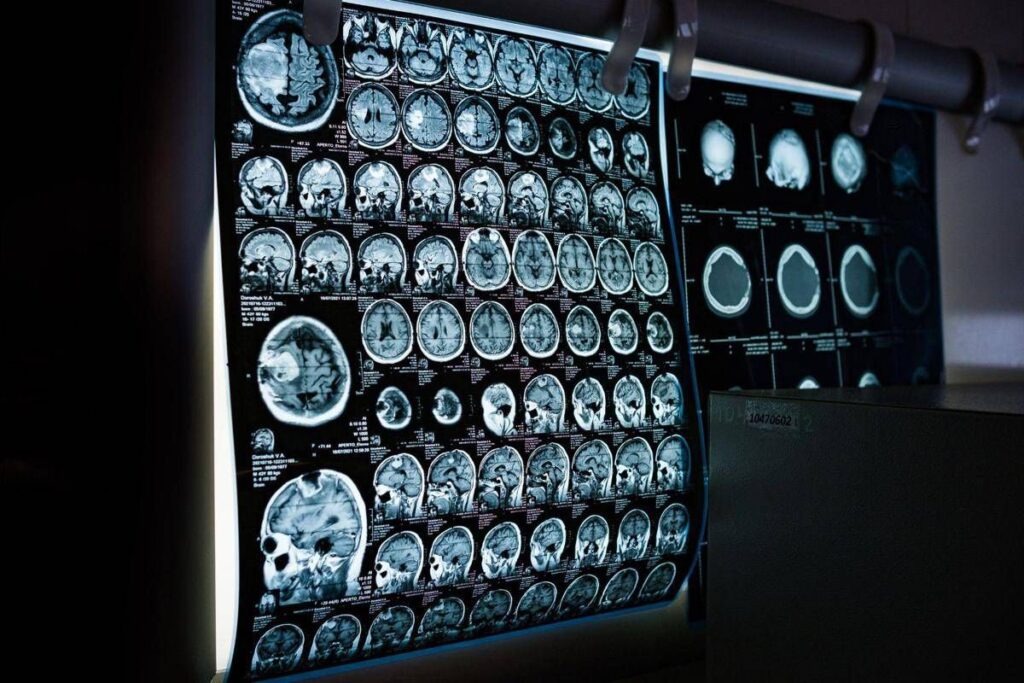

(Adnkronos) – In occasione della Giornata mondiale delle malattie rare 2026, che si celebra il 28 febbraio, la Società italiana di neurologia (Sin) rinnova il proprio impegno nel promuovere attenzione, consapevolezza e azioni concrete per i pazienti affetti da malattie neurologiche rare, un ambito che rappresenta una delle aree più complesse e in continua evoluzione. Queste patologie – informa la società scientifica in una nota – comprendono centinaia di condizioni differenti, spesso di origine genetica, che possono manifestarsi in età pediatrica o adulta e che sono frequentemente caratterizzate da un decorso progressivo e da un importante impatto funzionale. Nel loro insieme, queste patologie interessano un numero rilevante di persone e pongono sfide significative non solo sul piano clinico ma anche organizzativo, sociale ed economico, coinvolgendo l’intero sistema sanitario.

Negli ultimi anni, il panorama delle malattie neurologiche rare è stato profondamente trasformato dalla disponibilità di terapie innovative che stanno cambiando in modo concreto la storia naturale di alcune patologie. Tra queste rientrano, a titolo di esempio, le terapie enzimatiche sostitutive, le terapie di riduzione del substrato, gli oligonucleotidi antisenso, le terapie geniche e altre strategie avanzate attualmente in sviluppo clinico. Questi approcci terapeutici, già disponibili o in fase avanzata di sperimentazione per diverse condizioni neurologiche rare – illustrano i neurologi – rendono ancora più urgente una diagnosi tempestiva e una corretta stratificazione clinica dei pazienti. In molti casi, infatti, l’efficacia delle terapie è strettamente legata alla precocità dell’intervento e alla preservazione delle funzioni neurologiche residue.